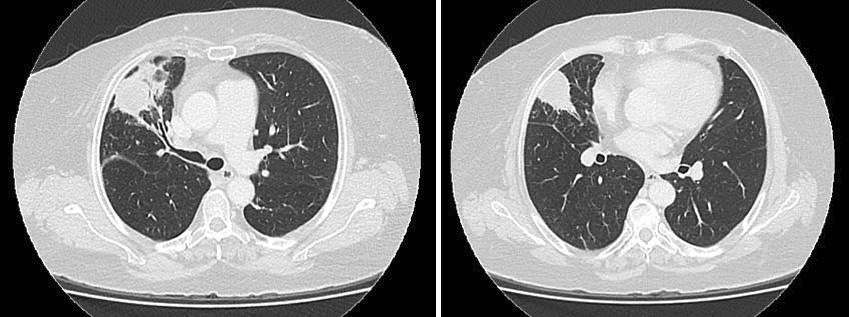

La paciente continuó con registros subfebriles diarios, marcada astenia y tos seca. Se interpretó el cuadro como posible neumonía organizativa y se inició tratamiento con meprednisona 40 mg al día. La paciente mejoró parcialmente, sin repetir eventos febriles; por lo que al mes de iniciado el tratamiento con corticoides, se comenzó su reducción. Durante el descenso, la paciente presentó hemoptisis moderada por lo que consultó nuevamente al servicio de emergencias. Los exámenes de laboratorio mostraron anemia de trastornos crónicos y reactantes de fase aguda elevados. Una nueva TC de tórax describió dos imágenes nodulares de bordes definidos, mayores a 15 mm, en lóbulo superior derecho y lóbulo medio. (Figura 4) Se escaló la dosis de meprednisona a 40 mg al día y se extendió el perfil reumatológico donde se obtuvo resultado de anticuerpos anti membrana basal glomerular que fueron positivos.

Imágenes nodulares de bordes definidos mayores a 15 mm en lóbulo superior derecho y lóbulo medio.